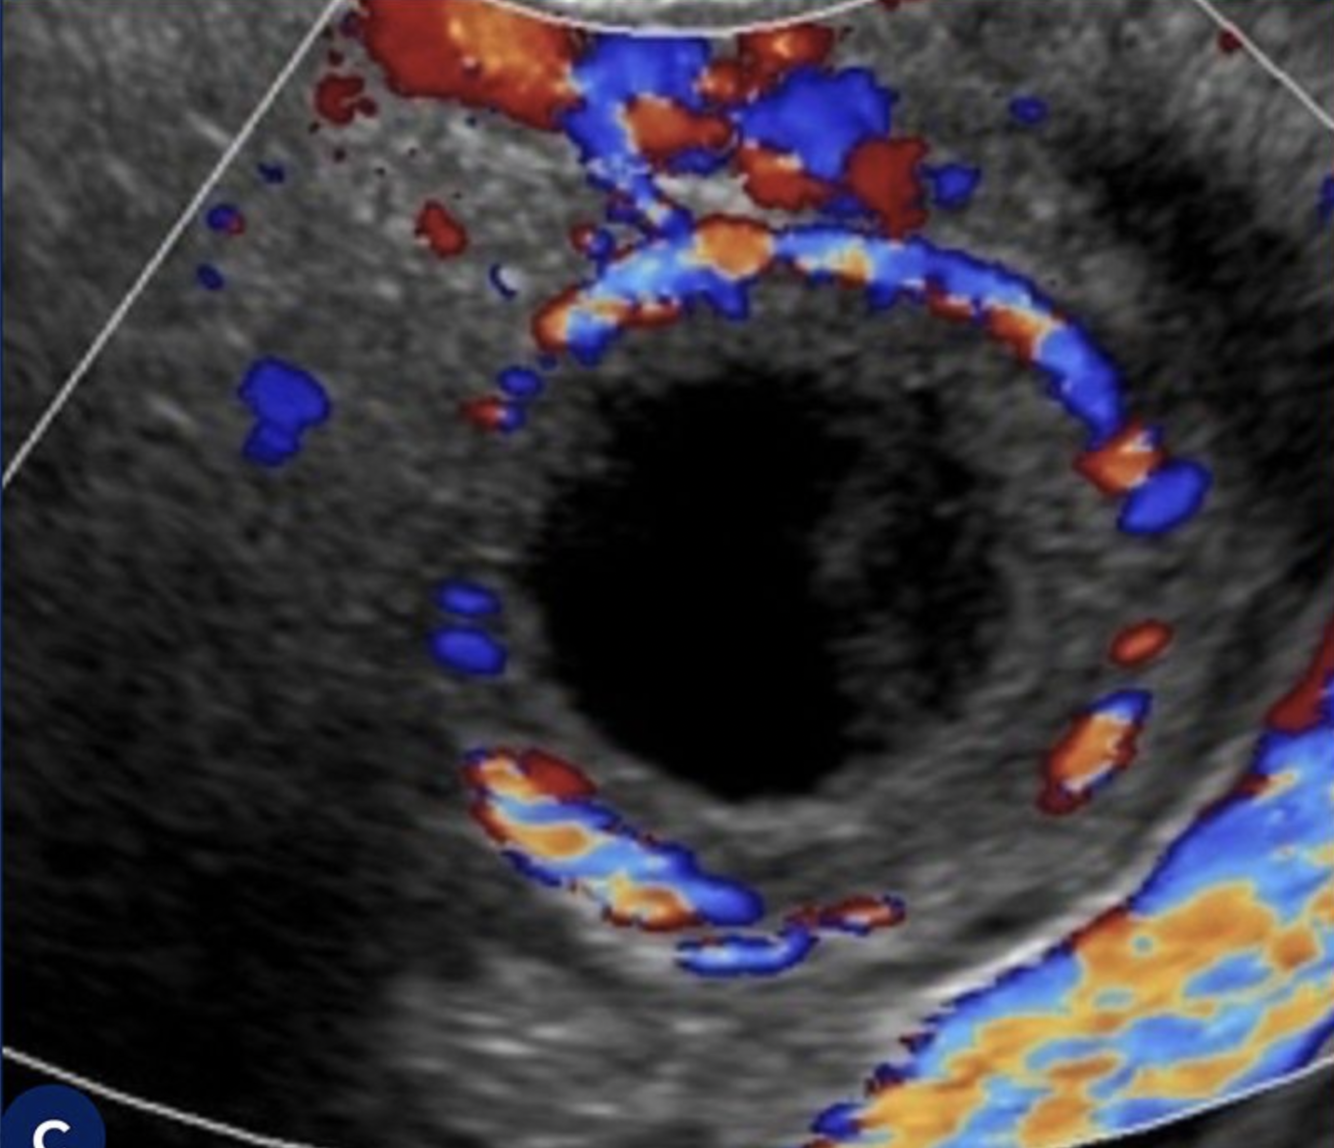

Q

Qual o diagnóstico ?

A

Pólipo Endometrial (Massa com ecogenicidade similar ou maior do que a do endométrio, o que a diferencia do Mioma)